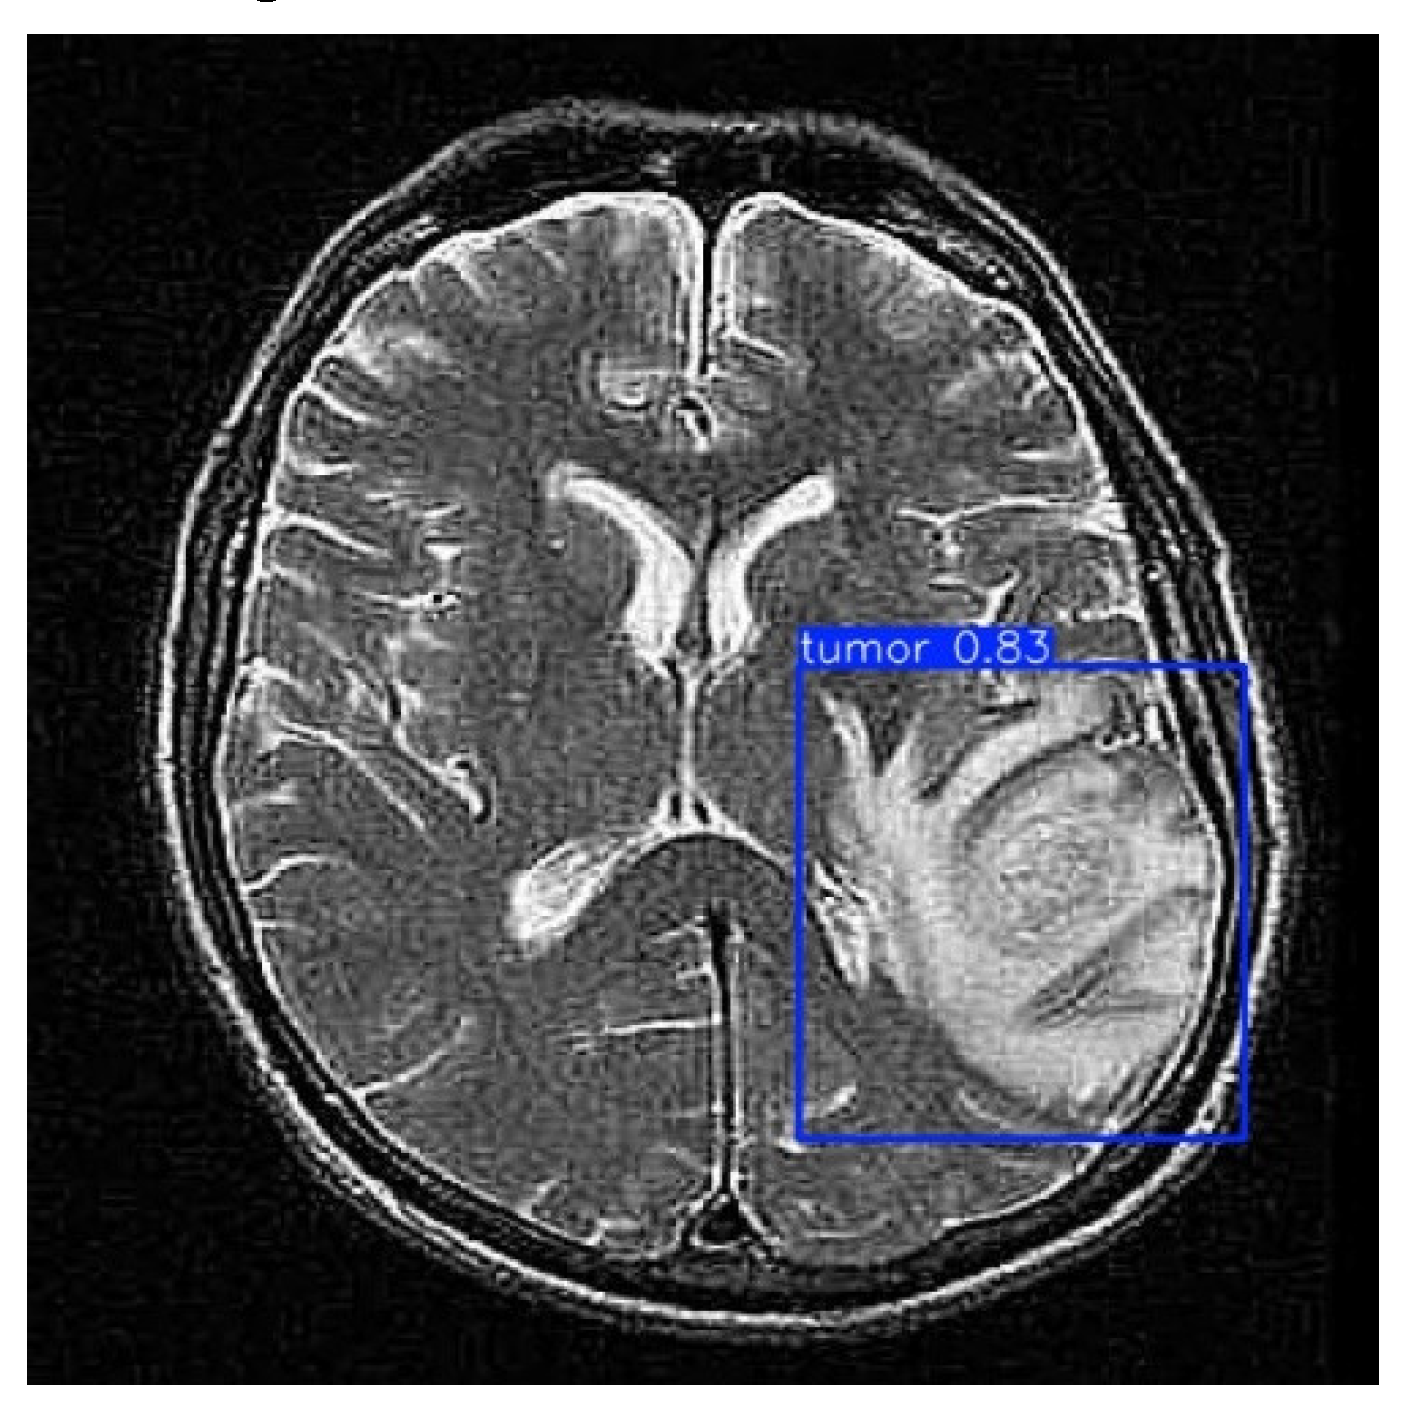

3.6. Validation and Final Prediction

With the model trained and evaluated, it is validated on a different data set than the training one. Using the !yolo task=detect mode=val command, the model’s ability to generalize to new data is validated. Subsequently, the final prediction is performed on a set of test images using the !yolo task=detect mode=predict command, with a confidence threshold of 0.25. The output images were stored and visualized, allowing for a final performance review and ensuring the model’s effectiveness in tumor detection, as illustrated in Figure 3.

As illustrated in Figure 6, after processing through the proposed model, it automatically identifies regions associated with cancer by incorporating blue bounding boxes. Additionally, each detection is accompanied by a confidence percentage, indicating the certainty level of the model’s predictions.

To evaluate the model’s ability to generalize brain tumor detection beyond a specific cancer type, tumors of various sizes were considered. The results indicate that the model correctly identifies affected areas regardless of variations in size or tumor coloration. In some cases, tumor regions appear white, in others gray, and some even combine both shades. This behavior suggests that the model possesses a high generalization capacity, accurately detecting cancerous regions regardless of their size, color, or location within the image. This effectively demonstrates the “Theoretical Foundations and Applications of Deep Learning Techniques” through computer vision.

Figure 3. Tumor prediction.